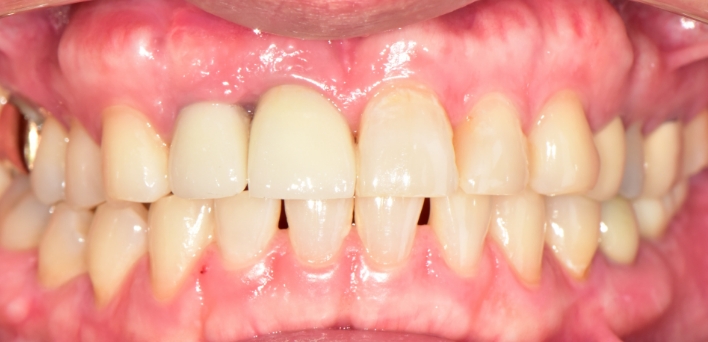

임플란트 : 손 ** 님 (50대)

치아가 있다는게, 아직도 정말 꿈만 같아요.

After After

2020.02.30

위, 아래 6개씩 식립

디지털 풀아치 임플란트

처음 이가 몇 개 빠졌을 때는 신경을 쓰지 않았는데..

모든 이가 빠지고 나서 제대로 먹지 못해서 살도 빠지고 체력도 떨어져서 기운이 없었어요..

임시 치아라고 조심하라고 하셨는데 수술하고 맛동산까지 먹었습니다.

제가 직접 후기를 인터뷰해서 저같은 많은 분들께서 위로와 용기를 얻으셨으면 합니다.

수술 생각도 못하다가 더서울치과를 만나서 진작에 할 걸 싶습니다. 너무 감사합니다.